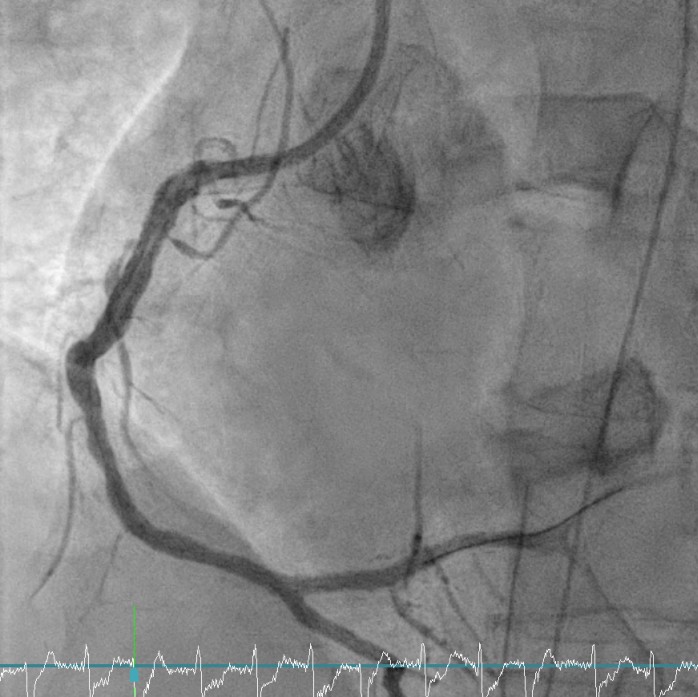

Relevant Catheterization Findings

Coronary angiography revealed critical left main and triple-vessel coronary artery disease. The right coronary artery and posterolateral branch were totally occluded, serving as infarct-related lesions. TIMI flow improved from 0 to 3 after deployment of two drug-eluting stents in the RCA and RCA-PL. Residual severe disease in the left main, LAD, and LCX was reserved for staged PCI. Periprocedural VT was defibrillated twice (200 J) under VA-ECMO and IABP support.

Staged PCI (Mar 6): One DES was placed in the LCX and one DCB in the LM–LCX segment. ECMO and IABP were successfully removed on March 8. Continuous renal replacement therapy was started for acute kidney injury. Brain CT showed watershed infarcts and a small subarachnoid hemorrhage, followed by gradual neurological recovery.

Staged LM–LAD PCI (Apr 18): Two DES were deployed in the LM–LAD under mechanical and pharmacologic support.